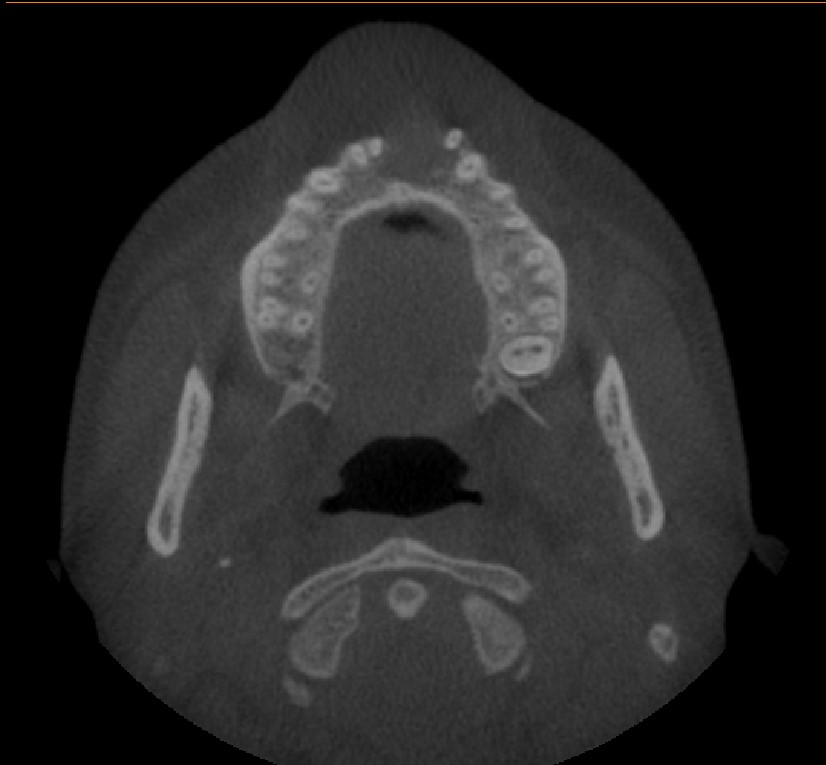

Radiological findings

• CBCT showing well defined unilocular radiolucency with cortical destruction present in anterior maxilla